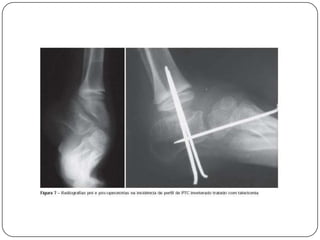

RadiografiaA radiografia avalia os ossos do pé, mas o exame é de pouca importância porque se encontram poucos ossos ossificados e não aparecem bem na radiografia.Deve-se avaliar o ângulo entre o eixo longitudinal do tálus e do calcâneo que se encontra diminuído ( ângulo de Kite)

>Ângulo de Kite  maior o varismo< Ângulo de Kite  maior o valgismo

TratamentoO objetivo do tratamento é um pé Plantígrado , indolor, flexível, com boa força muscular e que permita o uso de calçado comum.O tratamento é iniciado o mais precocemente possível , por meio de manipulação e trocas de gesso.Caso não se obtenha um resultado satisfatório, indica-se o tratamento cirúrgico.

O tratamento cirúrgico é indicado após 9 meses, e é realizado uma liberação das estruturas mediais e posterolaterais do pé, com a correção da deformidade e fixação da articulação talonavicular e subtalar.Em crianças com mais de 4 anos e deformidades rígidas pode-se usar a talectomia.